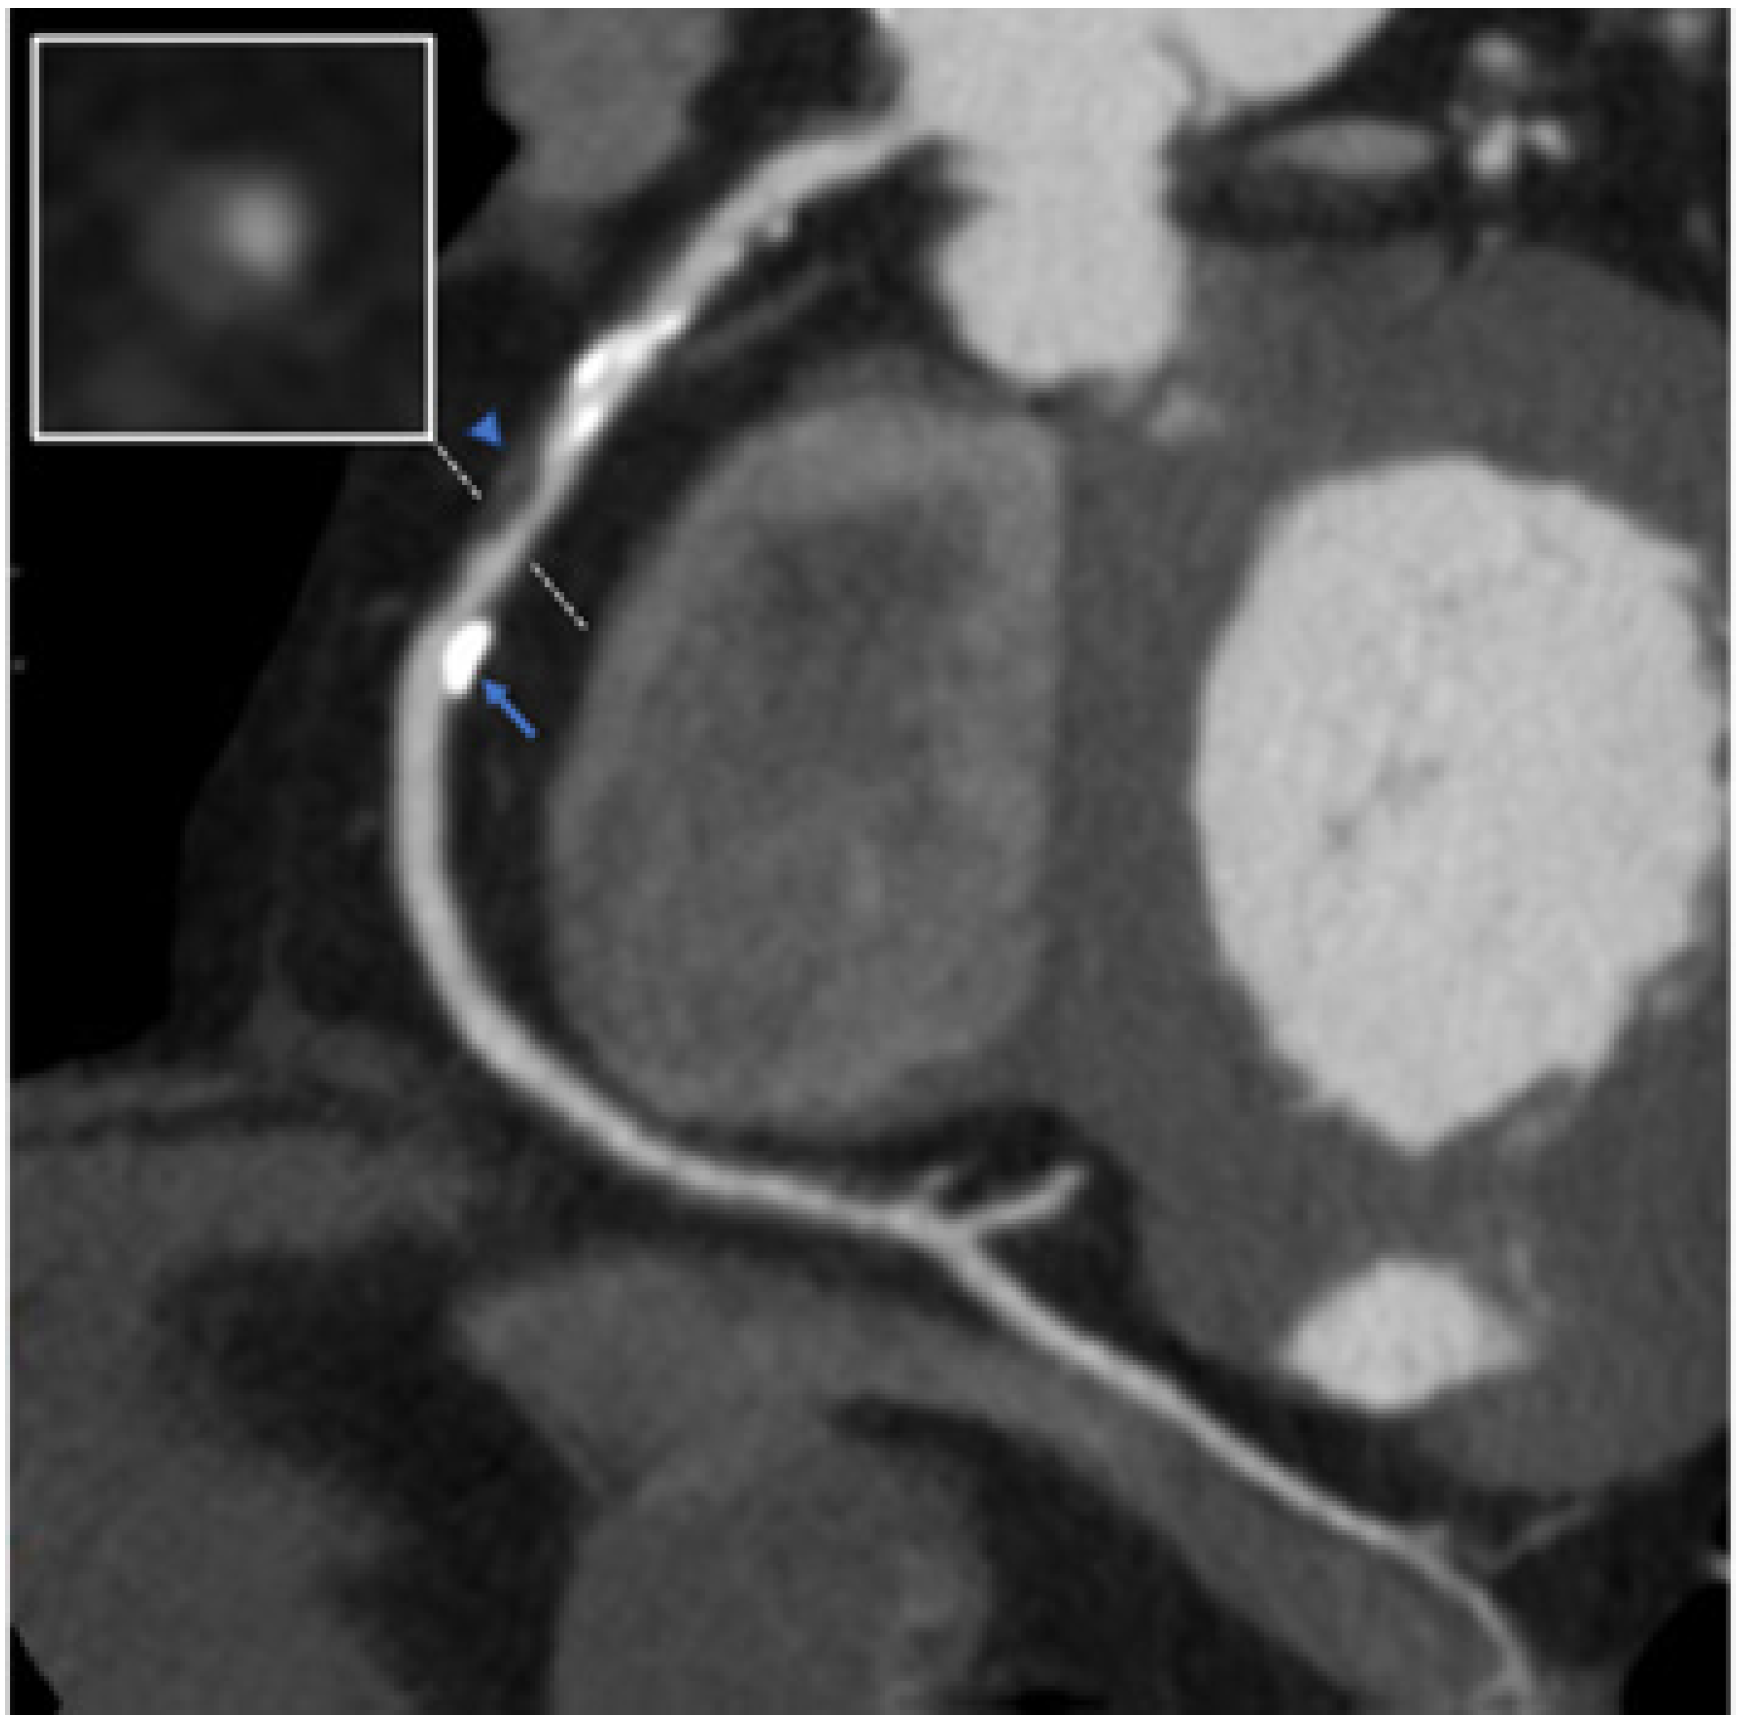

7.2. Coronary Fistula